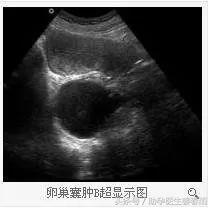

结果如下:子宫内0.2x0.2cm,右侧卵巢囊肿6.1x5.1Cm

卵巢囊肿

卵巢囊肿是常见的妇科疾病,各种年龄均可患病,但以20—50岁的女性最为多见。

一、超声检查